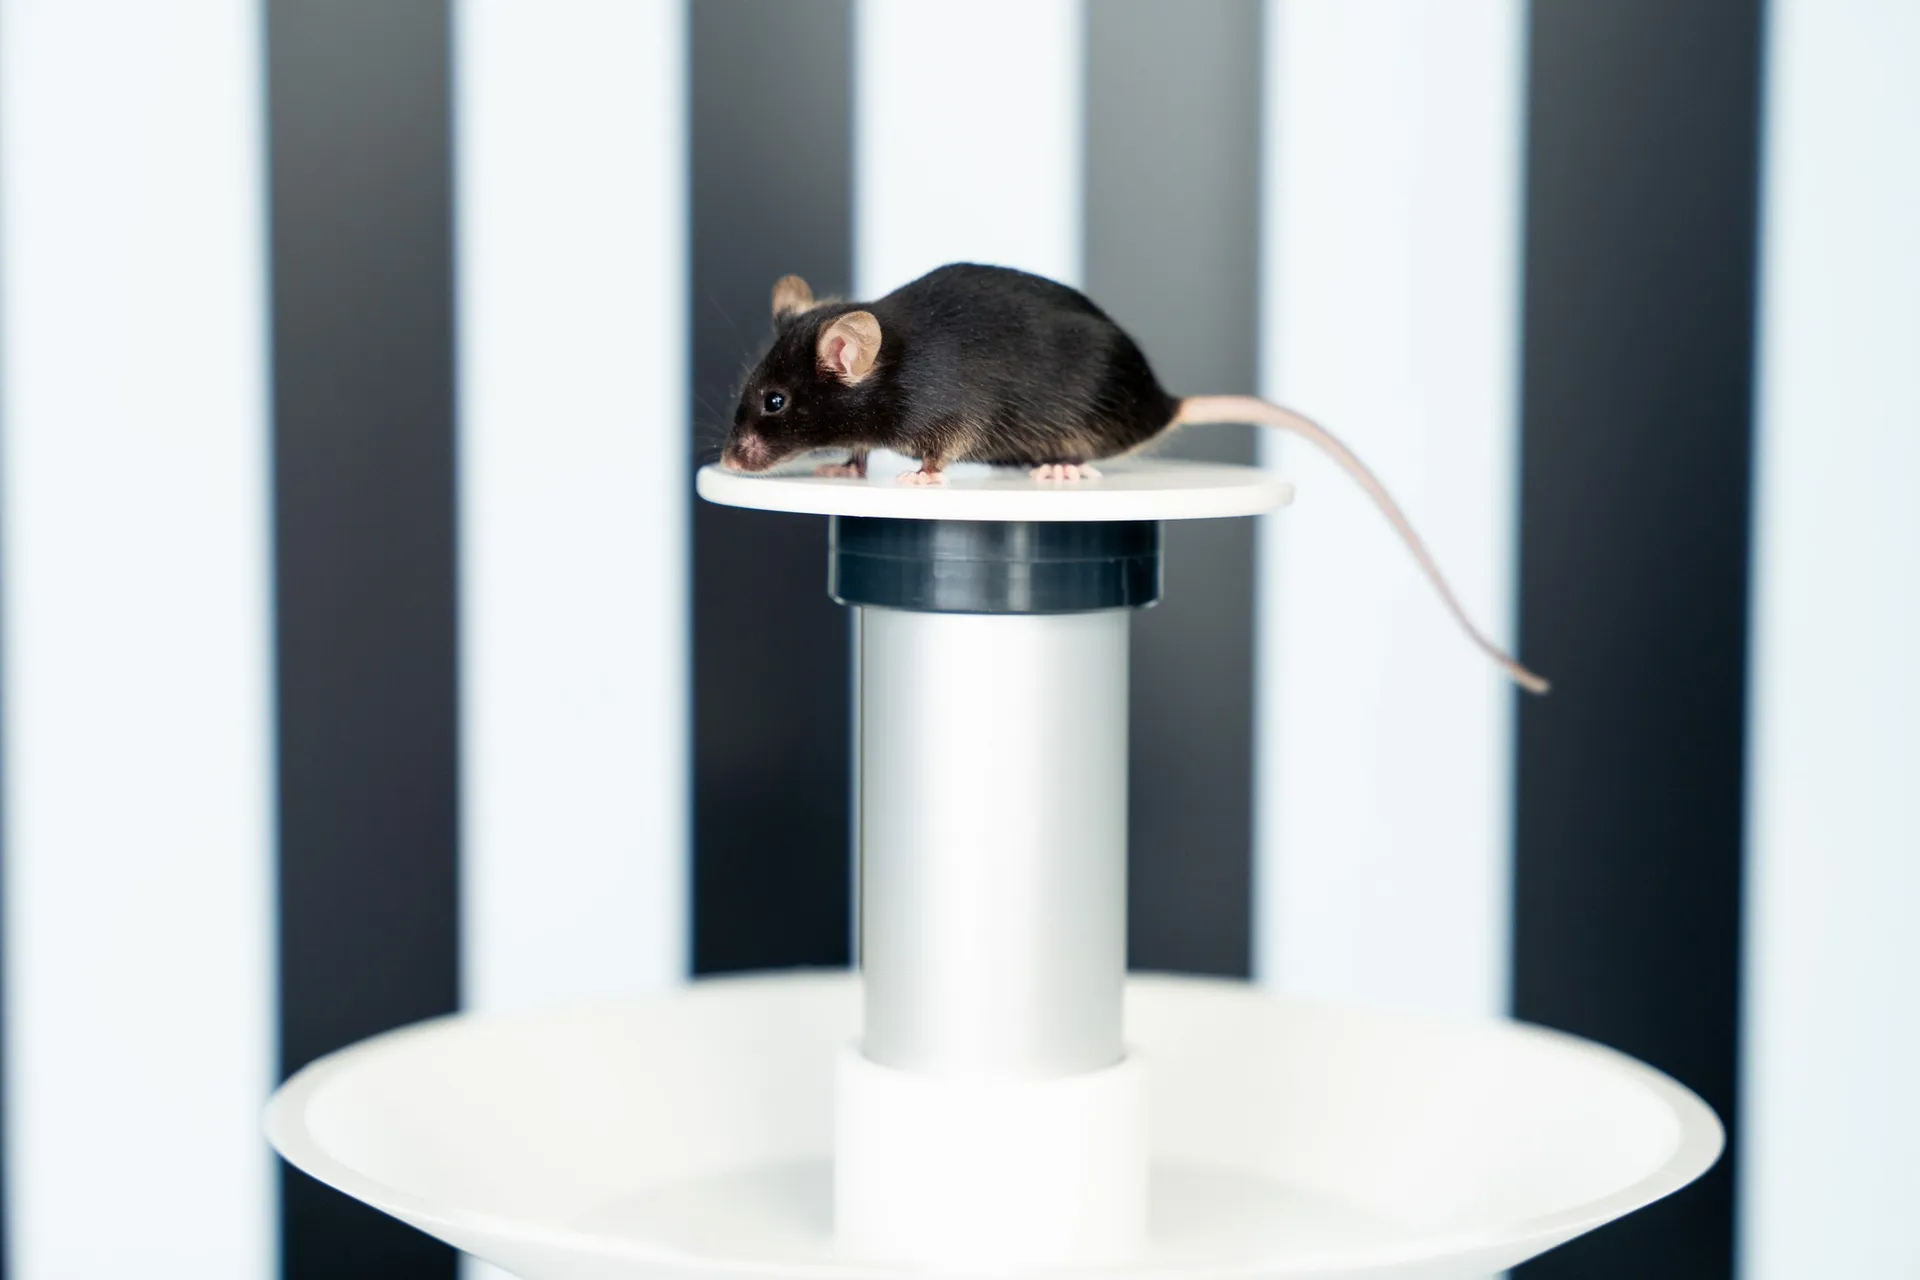

Retinal morphology is monitored utilizing spectral-domain optical coherence tomography (SD-OCT), while visual function is evaluated using flash electroretinography (fERG) and optomotor response (OMR). These non-invasive techniques enable comprehensive monitoring of disease progression with longer follow-up periods. Additionally, we provide histology and immunohistochemical stainings, enabling detailed analysis of tissue morphology and molecular markers to assess disease progression and treatment efficacy.

-Behavioral assessment (OMR)

o Visual acuity and contrast sensitivity

Learn moreOptomotor Reflex

Experimentica offers behavioral assessment and optomotor response testing to evaluate visual acuity and contrast sensitivity in rodent models.